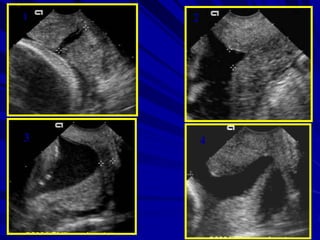

the progressive shortening

detected by serial sonar,

funneling (width and length),

v-shaped lower uterine segment

and dynamic cervical changes

with fundal or suprapubic

pressure.

1 2

3 4